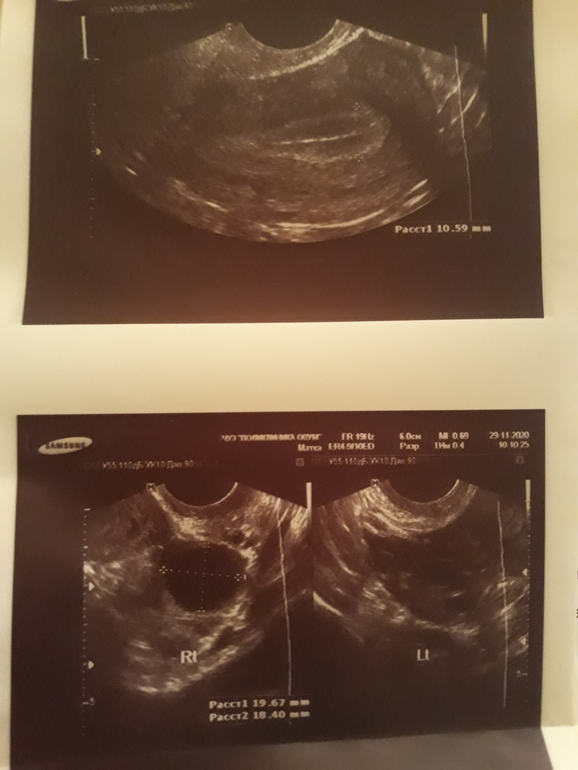

На 10 д.ц в 11 утра по УЗИ ДФ в правом яичнике размер 16мм, 11 дц в 11 утра тест на овуляцию отрицательный, 12 дц в 11 утра тест на овуляции положителтный, сегодня 13 дц в 11 утра УЗИ ДФ уже 19мм(фото прикреплю). Как думаете, завтра случится овуляция?